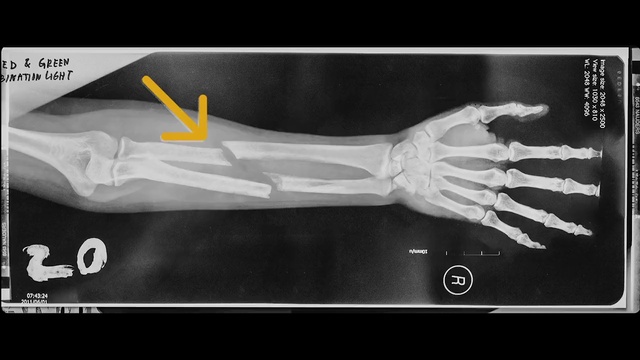

Best Video References: Fracture

Featured videos selected by a smart neural network algorithm